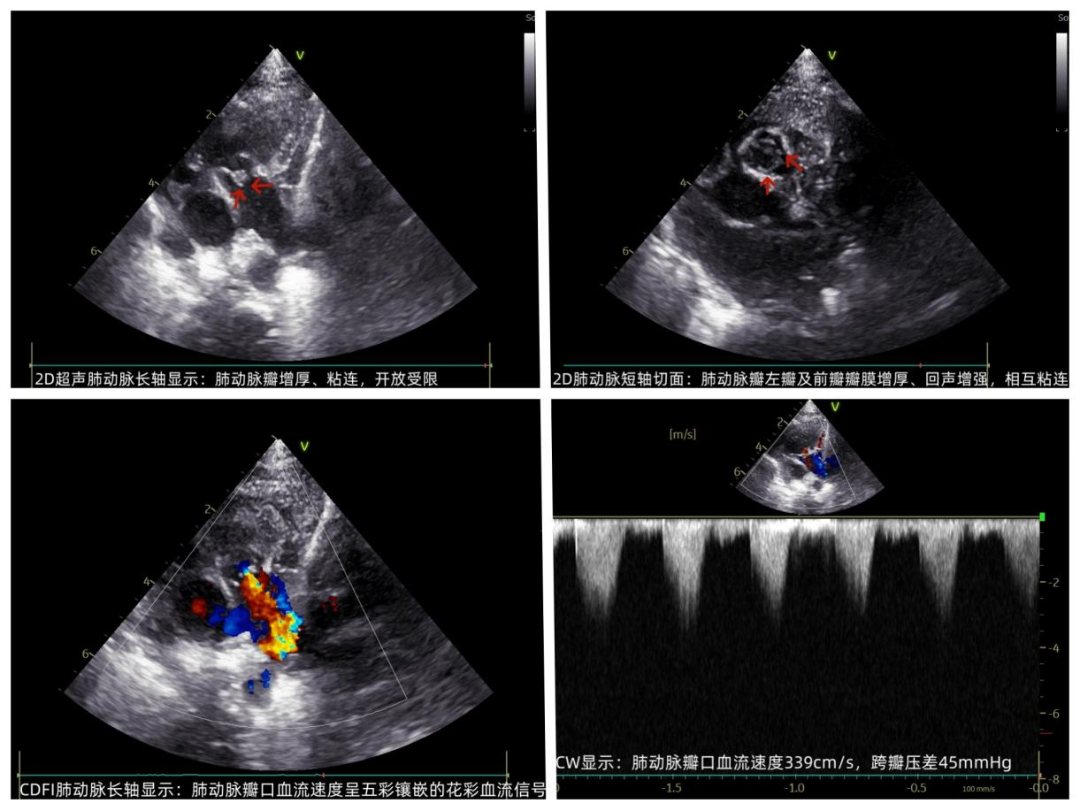

午夜12点,城市沉浸在宁静酣睡中时,呼和浩特市第一医院超声医学科灯火通明,值班医生坚守岗位随时准备出发。此时值班室电话铃响起,是新生儿监护室紧急呼叫——一名出生不到72小时的新生儿因血氧水平低,急需超声医学科进行心脏评估查找病因,值班医生推着床旁超声机一路小跑来到患儿旁开始了细致的检查,小小的身体伴随着急促的喘息,由于患儿缺氧严重、躁动不安,检查过程并不顺利,同时发现患儿肺动脉瓣异常增厚、流速增高超过高限,考虑肺动脉瓣发育畸形。超声急诊医生检查完为确保结果完整可靠,第二日交班叮嘱接诊医生要进一步检查,遂超声门诊开通“绿色通道”,确保氧气供给安全时间内完成检查,检查中发现患儿动脉导管处约3mm的窗型回声失落,伴随大血管水平左向右分流,确诊为"肺动脉瓣狭窄合并动脉导管未闭"。同时超声科为此类新生儿开辟"先心病绿色通道",为新生儿的生命安全保驾护航。

图为患儿心脏超声图像

图为患儿心脏超声图像科普知识